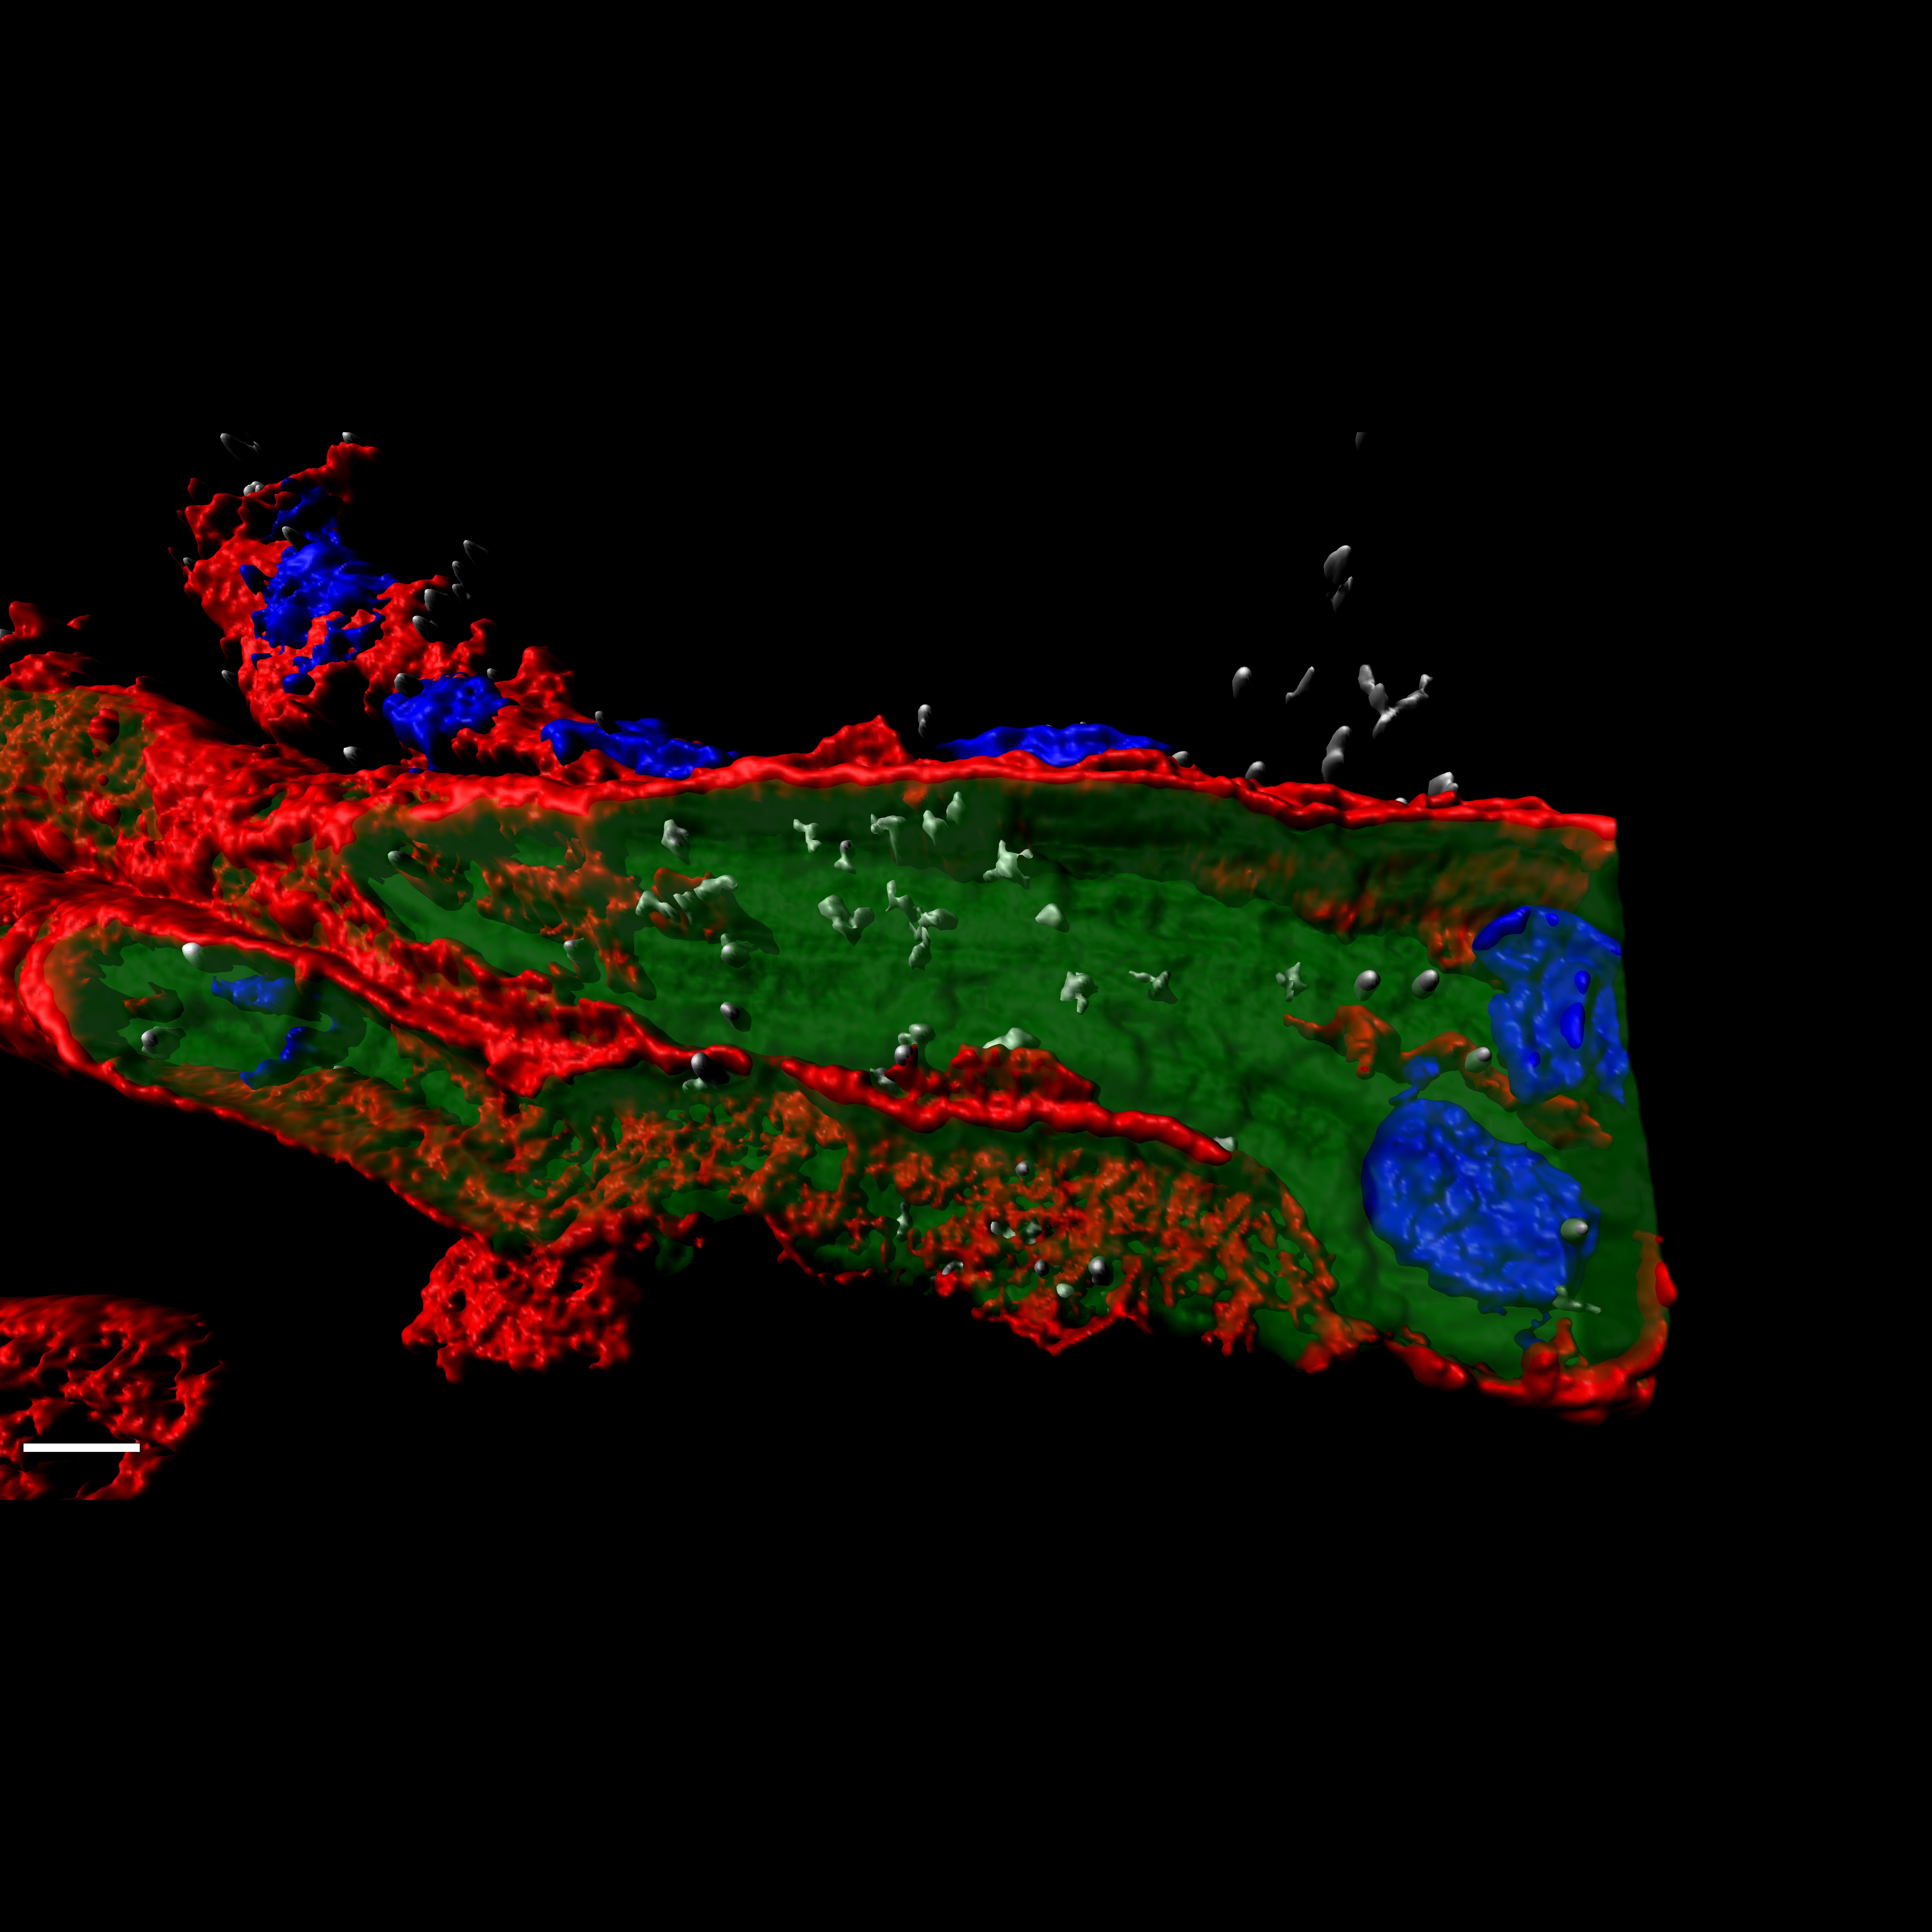

Una investigación experimental con cultivos 3D desvela un nuevo mecanismo implicado en el desarrollo del cáncer de páncreas y de pulmón